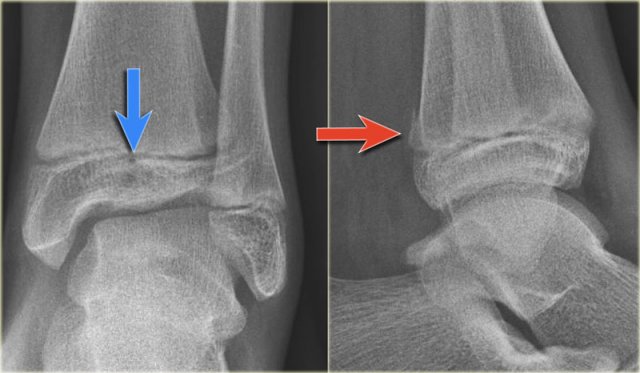

Linear lucency indicating a fracture of the posterior malleolus Linear lucency indicating a fracture of the posterior malleolus

When we study the radiographs of a patient with an ankle injury, we have to study the region of the posterior malleolus very carefully.

In many cases there is only a small gap between the fracture parts and detection depends on optimal radiography and a high level of suspicion.

The images show an obvious Weber B fracture.

On the AP-view the linear lucency is the clue to a tertius fracture (red arrow).

It results from subtle malalignment of the fracture fragment.

Likewise in some cases malalignment can result in a linear density.